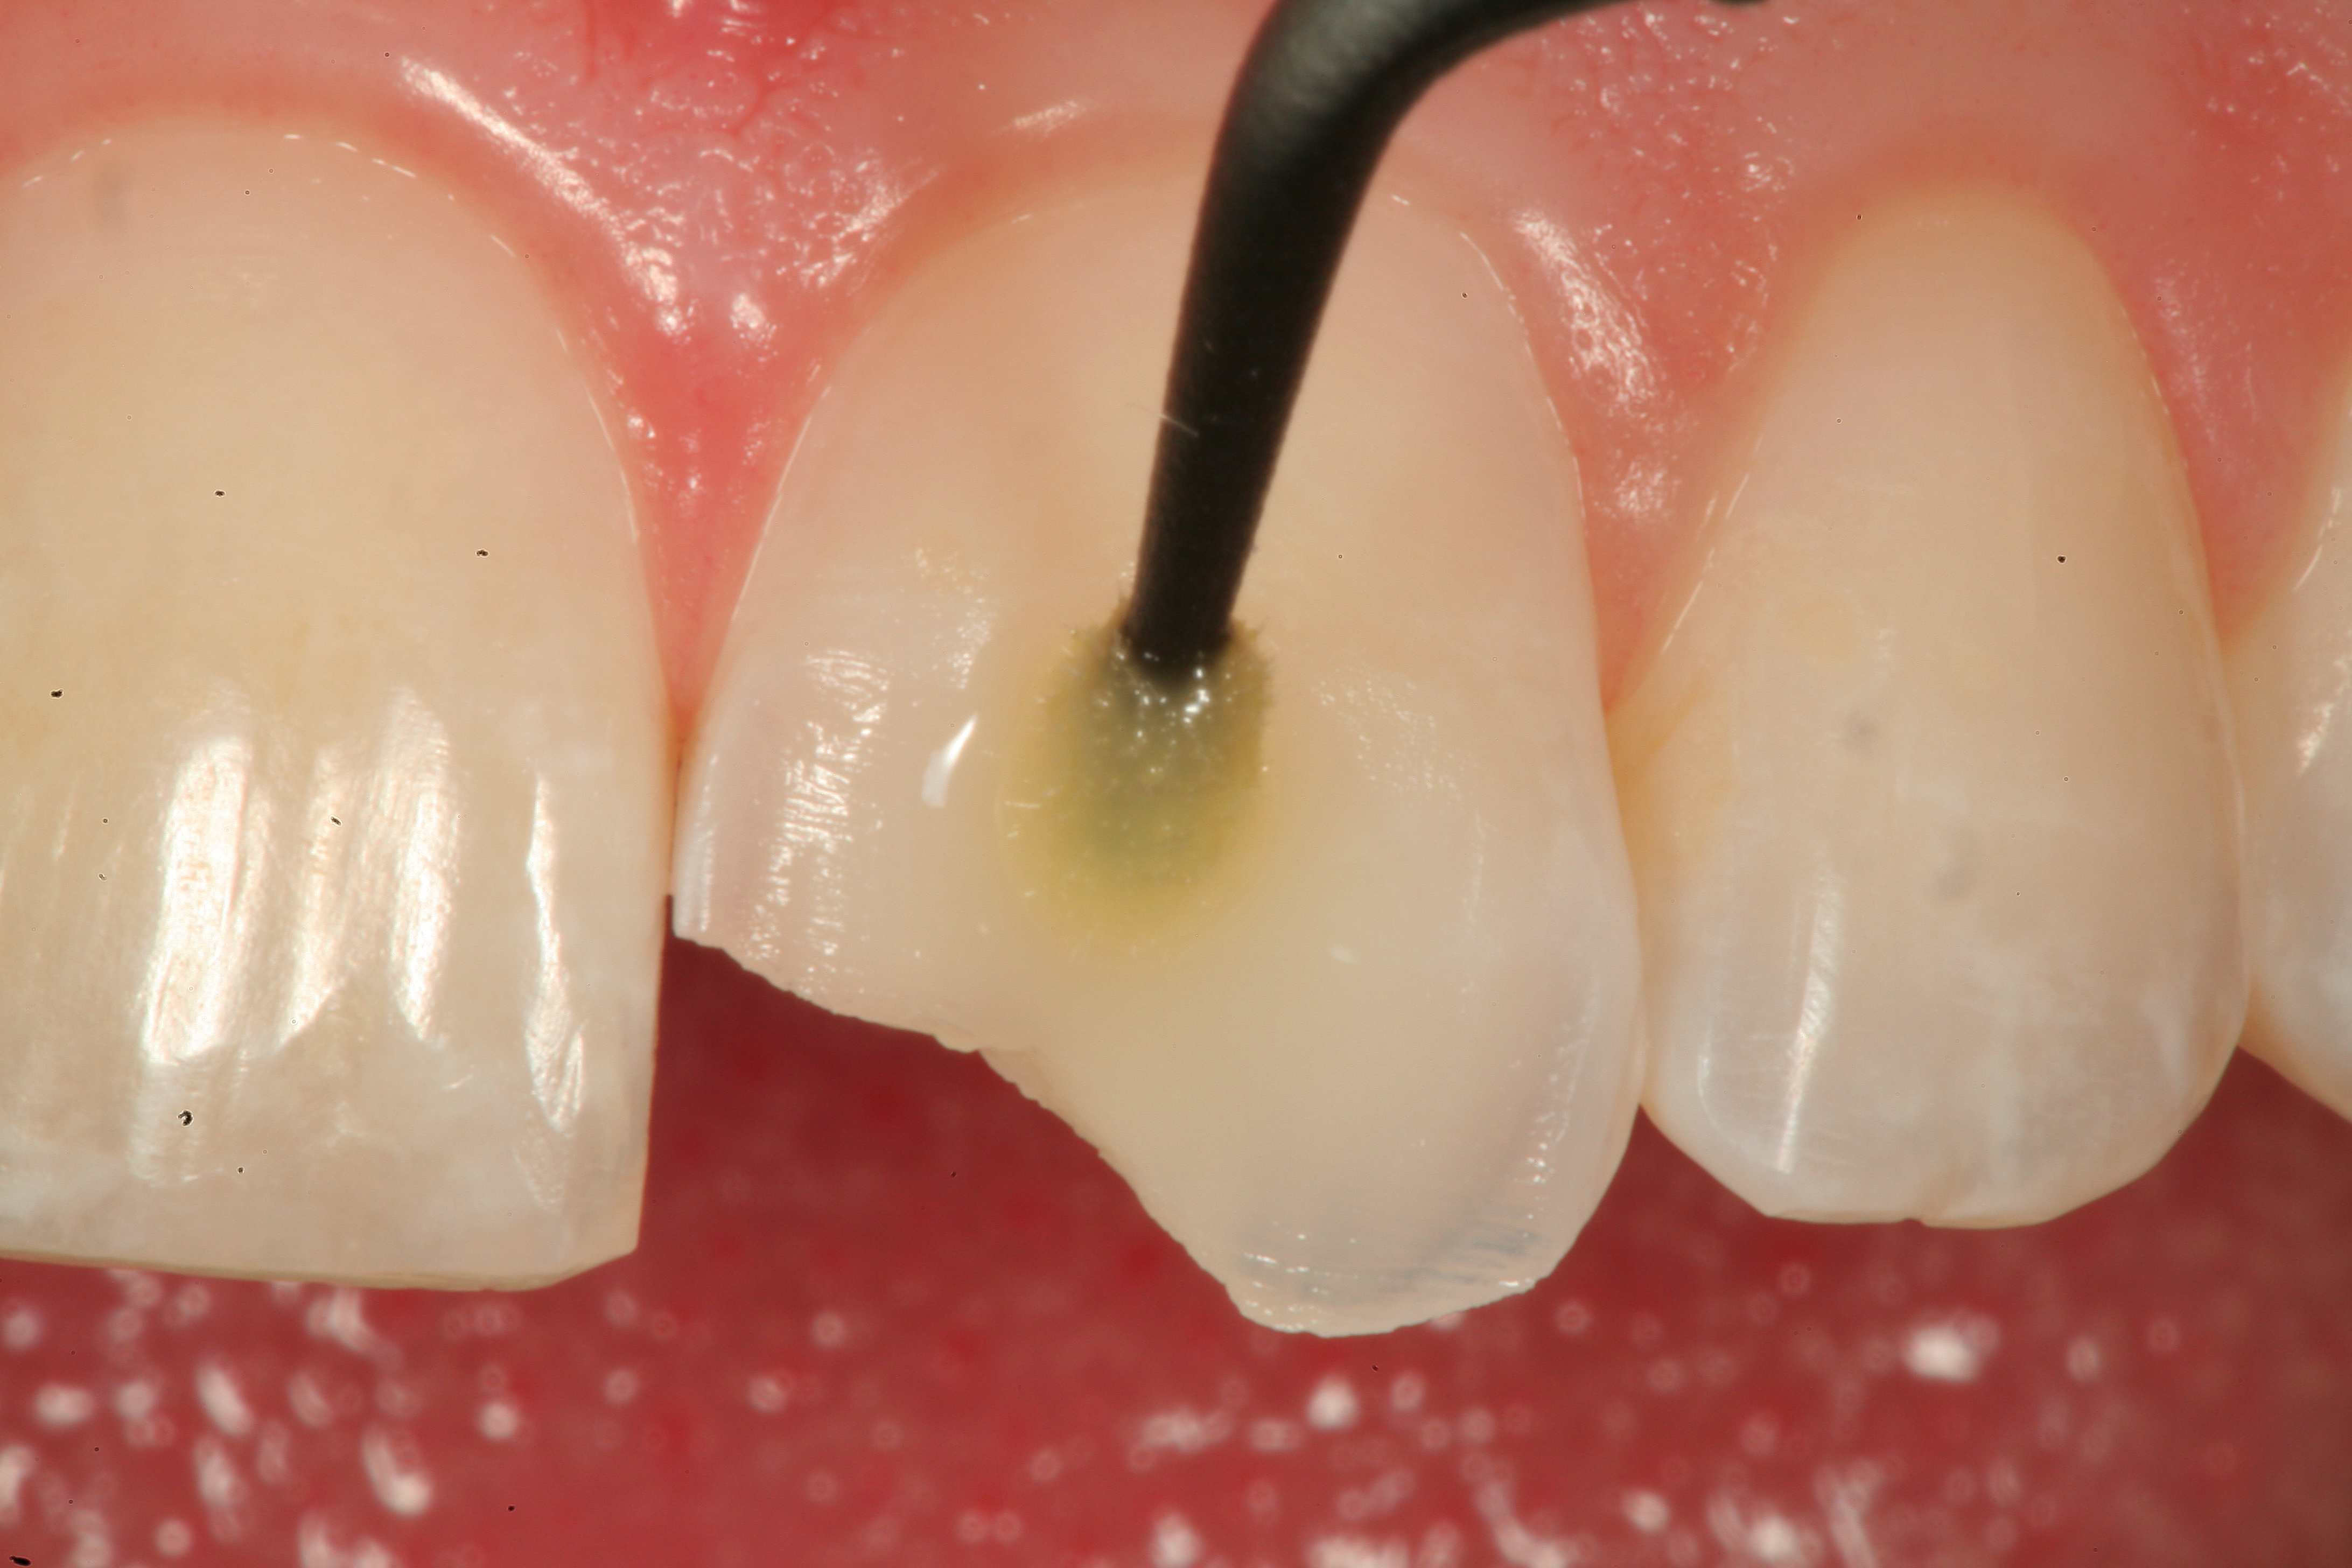

Fig 12. A Class IV mesial incisal fracture is shown from the facial aspect on tooth No. 9.

Figure 12